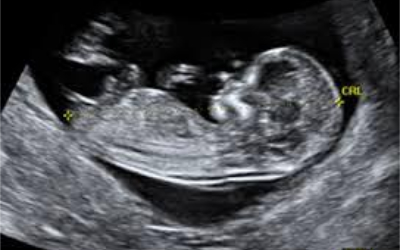

¿Cuáles son algunas de las razones para hacerse un ultrasonido? Su profesional de la salud utiliza el ultrasonido para controlar la salud y el desarrollo de su bebé, y para ayudar a calcular la fecha prevista de parto. El ultrasonido comprueba varias cosas, por...

El ultrasonido utiliza ondas sonoras para producir fotografías de las estructuras internas del cuerpo. Se utiliza para ayudar a diagnosticar las causas de dolor, hinchazón e infección en los órganos internos del cuerpo, y para examinar al bebé en una mujer embarazada,...